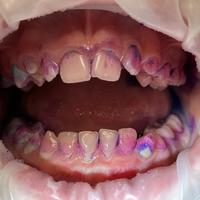

Коротко о бутылочном кариесе